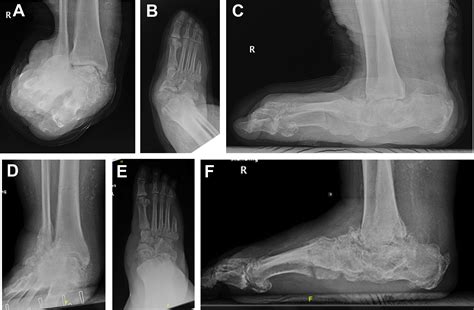

At its core, Charcot Arthropathy Foot is a progressive condition. Because the patient cannot feel the micro-traumas caused by everyday movement, the joints begin to weaken and collapse. The bones may fracture, shift, or even dislocate, causing the foot to lose its natural arch and shape. In the medical community, this is frequently described as a "rocker-bottom" deformity, where the middle of the foot drops, creating a convex shape on the sole.

Diagnostic Procedures and Clinical Evaluation

Doctors typically diagnose Charcot Arthropathy Foot through a combination of clinical history and imaging. Physical exams are used to assess the range of motion and look for signs of neuropathy. Imaging is critical to differentiate Charcot foot from cellulitis or other bone infections.

X-ray Detects fractures, dislocations, and bone fragments.